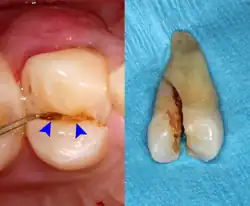

Unter einer Schrotkugelfraktur (auch Schrotkornfraktur, Hasenschrotfraktur) versteht man in der Zahnmedizin eine Längsfraktur eines Zahnes durch das ungewollte Aufbeißen auf einen kleinen starren Festkörper, demnach durch eine unnatürliche Gewalteinwirkung.[1][2][3] Die Beißkraft[Anm. 1], die beim Menschen normalerweise im Maximum 0,8 kN/cm² beträgt, kann sich um den Faktor 100 steigern, denn sie trifft dabei punktuell auf den Zahn auf.

Aufgrund der geringen Größe werden die kleinen Festkörper zwischen den Höckern der Krone gefangen, so dass laterale Ausdehnungen oder ein seitliches Ausweichen nicht möglich sind. Neben der Schrotkugelfraktur kann eine Zahnfraktur aber auch durch andere traumatische Einwirkungen entstehen, wie beispielsweise durch Unfälle oder Bruxismus (Zähneknirschen).

Neben dem Aufbeißen auf eine Schrotkugel kann eine solche Längsfraktur eines Zahnes durch ein Aufbeißen auf ein ungemahlenes Korn bei Vollkornprodukten, einen Kirschkern in Marmelade oder Fruchtkuchen, ein ungepopptes Maiskorn im Popcorn, einen Bestandteil („König“) eines Dreikönigskuchens, ein Steinchen im Salat oder Brot oder Nussschalenreste in der Nahrung verursacht werden.[4] Besonders gefährdet sind Prämolaren und Molaren (kleine und große Backenzähne), die an beiden Approximalseiten tief einschneidende Füllungen aufweisen.[5] Dies wurde unter anderem durch R. Trushkowsky, S. T. Talim und K. S. Gohil bestätigt, die festgestellt haben, dass die häufigste Ursache für ein Cracked-Tooth-Syndrom (englisch Zahnfraktur-Krankheitsbild), wie sie es nannten, ein solcher „Kauunfall“ ist.[6][7]

Initial verspürt man einen heftigen stechenden Schmerz. Ein Bruchfragment des Zahnes kann in seitlicher Richtung leicht beweglich sein. Der Zahn schmerzt in der Folge beim Kauvorgang, beziehungsweise reagiert auf Hitze, Kälte oder Süßigkeiten. Sollte nur ein winziger Bruchspalt entstanden sein, wobei ein Bruchfragment nicht beweglich sein muss, dringen im Lauf der Zeit Bakterien in den Bruchspalt ein und verursachen verzögert eine schmerzhafte Pulpitis (Zahnnerventzündung).

Je nach Art der Zahnfraktur kann der Zahn durch eine Zahnkrone, gegebenenfalls einschließlich einer endodontischen Behandlung (Wurzelkanalbehandlung) gerettet werden. In den meisten Fällen muss er jedoch extrahiert (entfernt) werden.